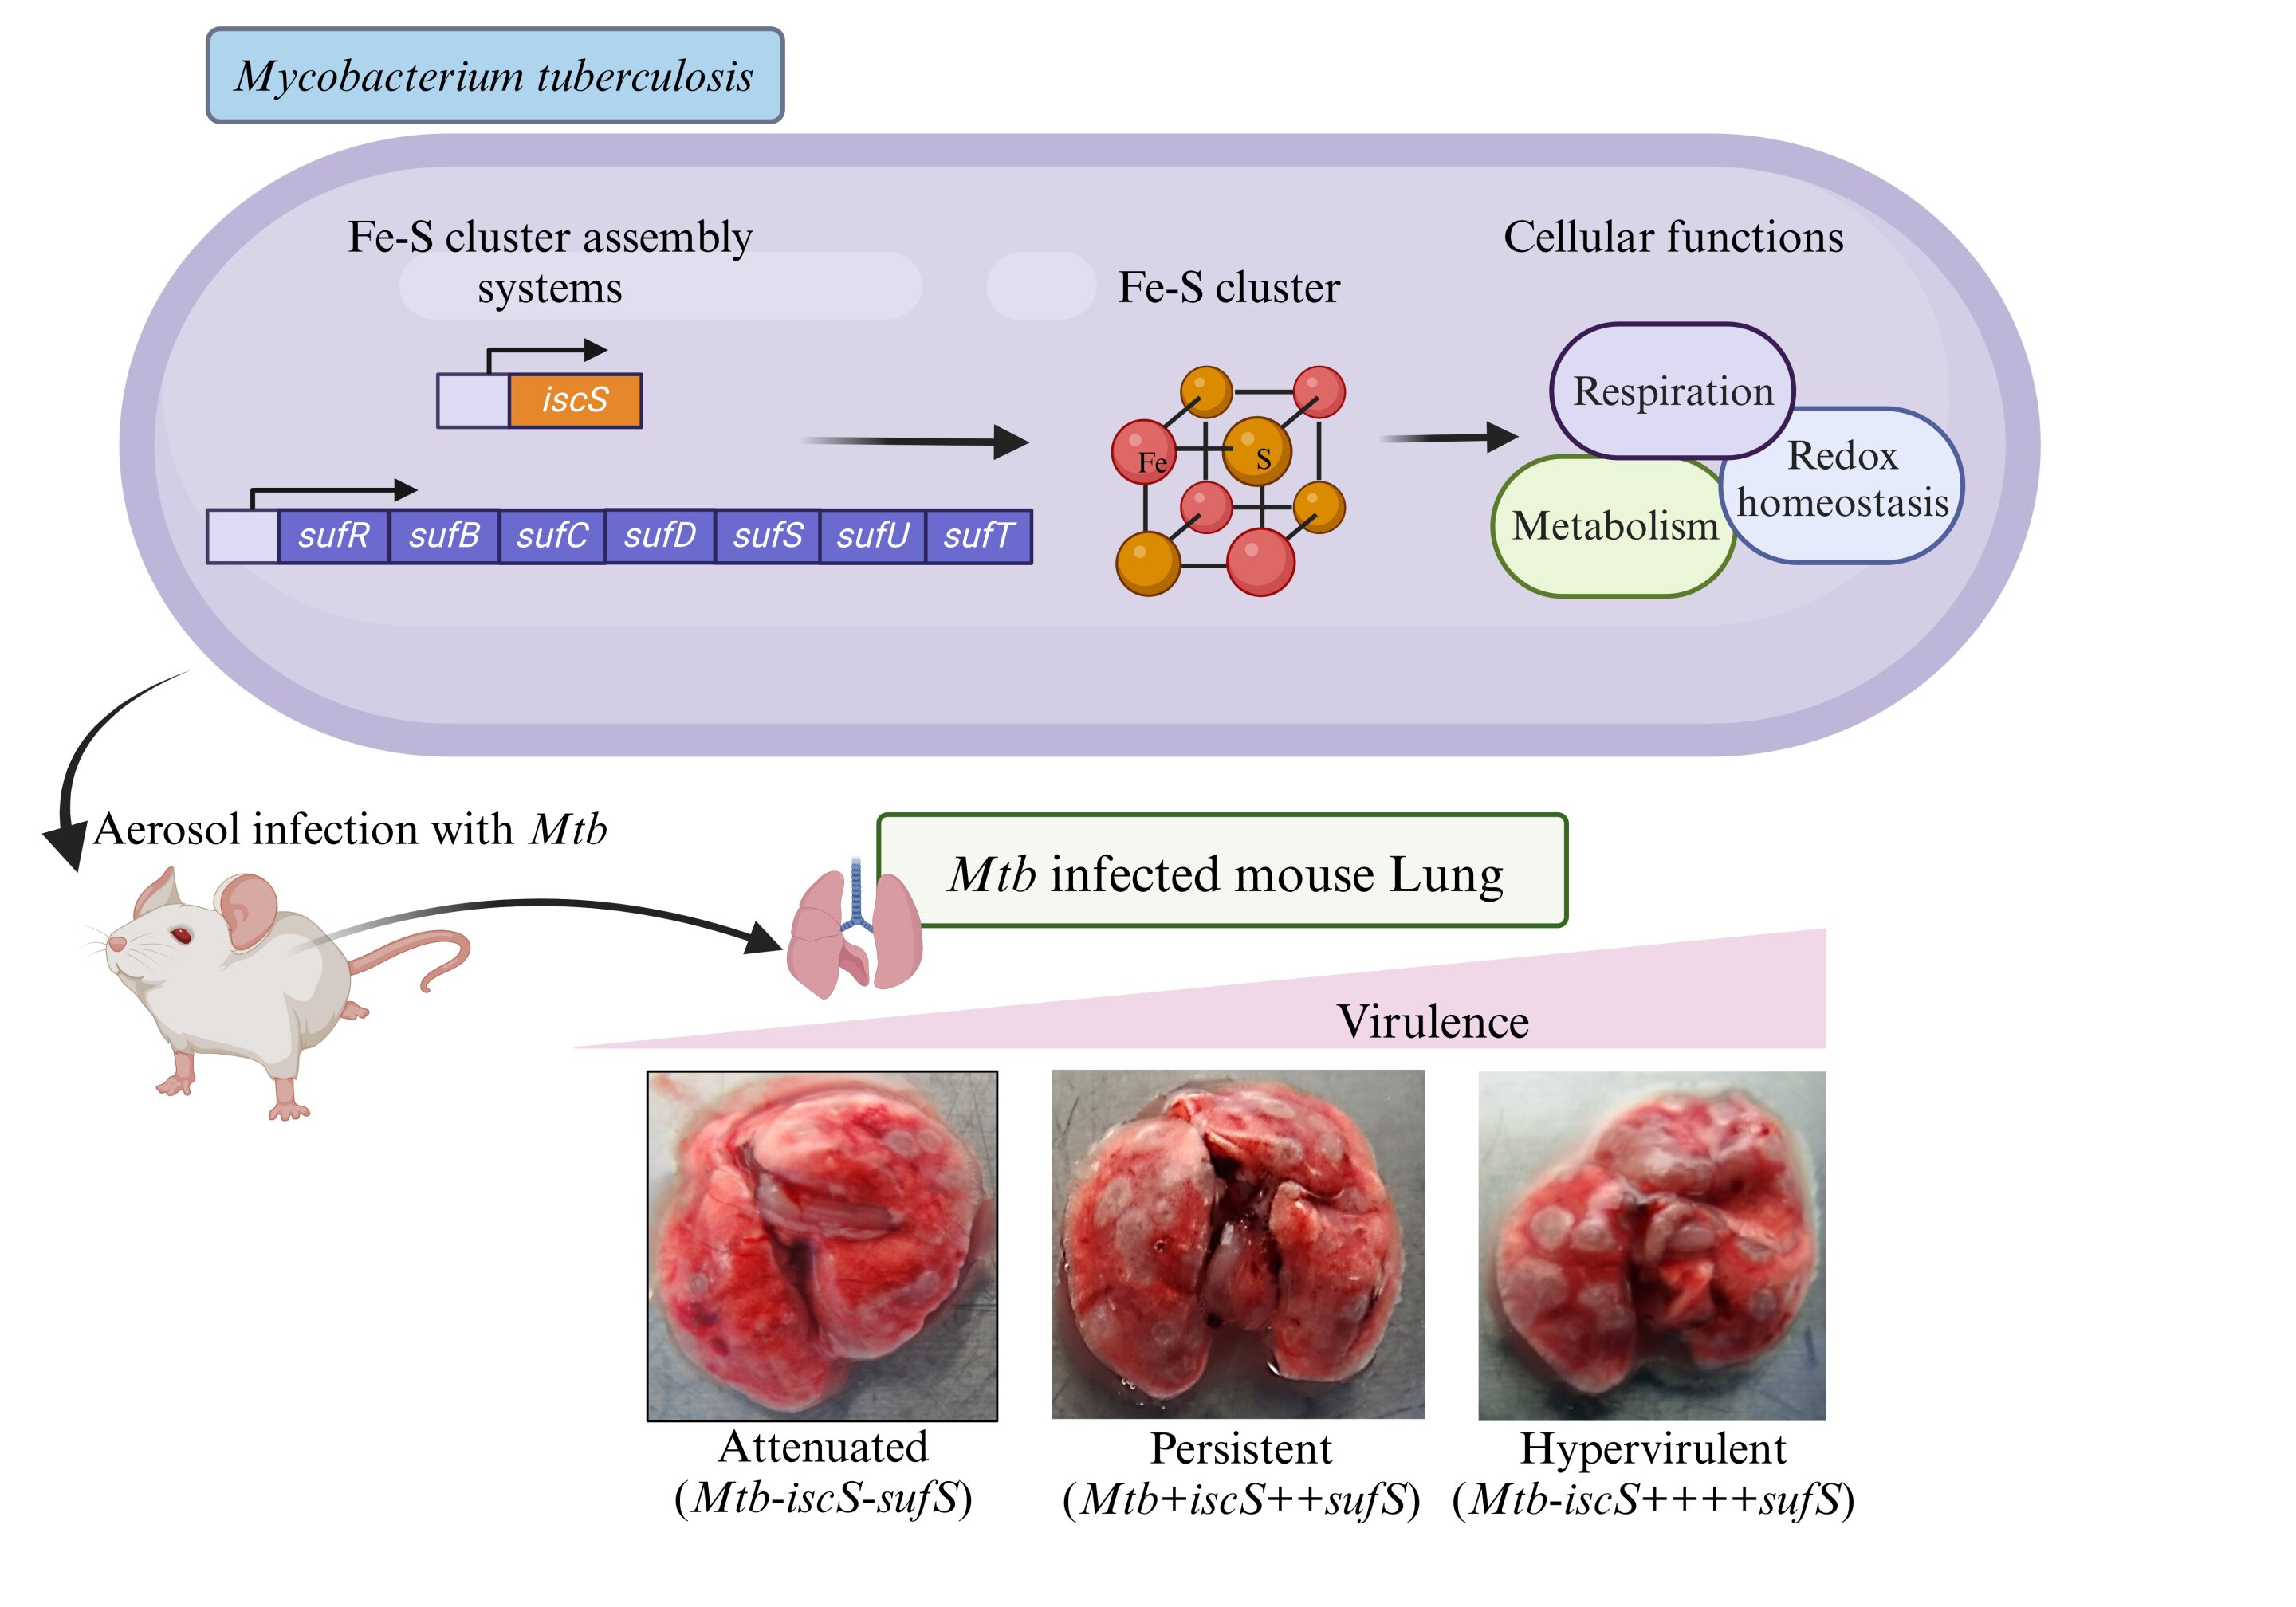

Cơ chế khiến khuẩn lao sống hàng thập kỷ trong cơ thể người

Các nhà nghiên cứu tại Viện Khoa học Ấn Độ (IISc), Trung tâm Khoa học Sinh học Quốc gia Ấn Độ (NCBS) và InStem đã khám phá ra một cơ chế quan trọng khiến cho vi khuẩn lao (TB) có thể tồn tại trong cơ thể con người hàng thập…